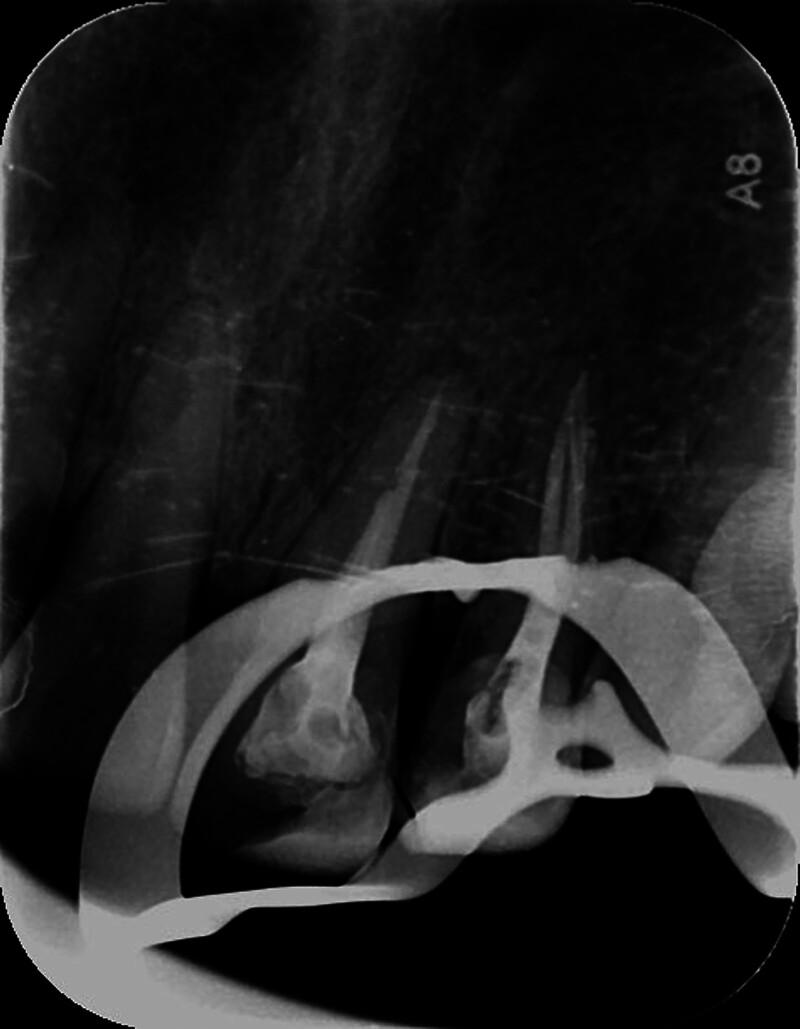

The patient underwent root canal retreatment involving the removal of old filling material, negotiation and preparation of the missed palatal canal using manual and rotary files, calcium hydroxide dressing, and final obturation with cold lateral compaction and gutta-percha.

患者接受根管再治疗,包括去除旧的充填材料,使用手动和旋转锉对遗漏的腭侧根管进行疏通和预备,氢氧化钙封药,最后采用冷侧方加压和牙胶进行充填。